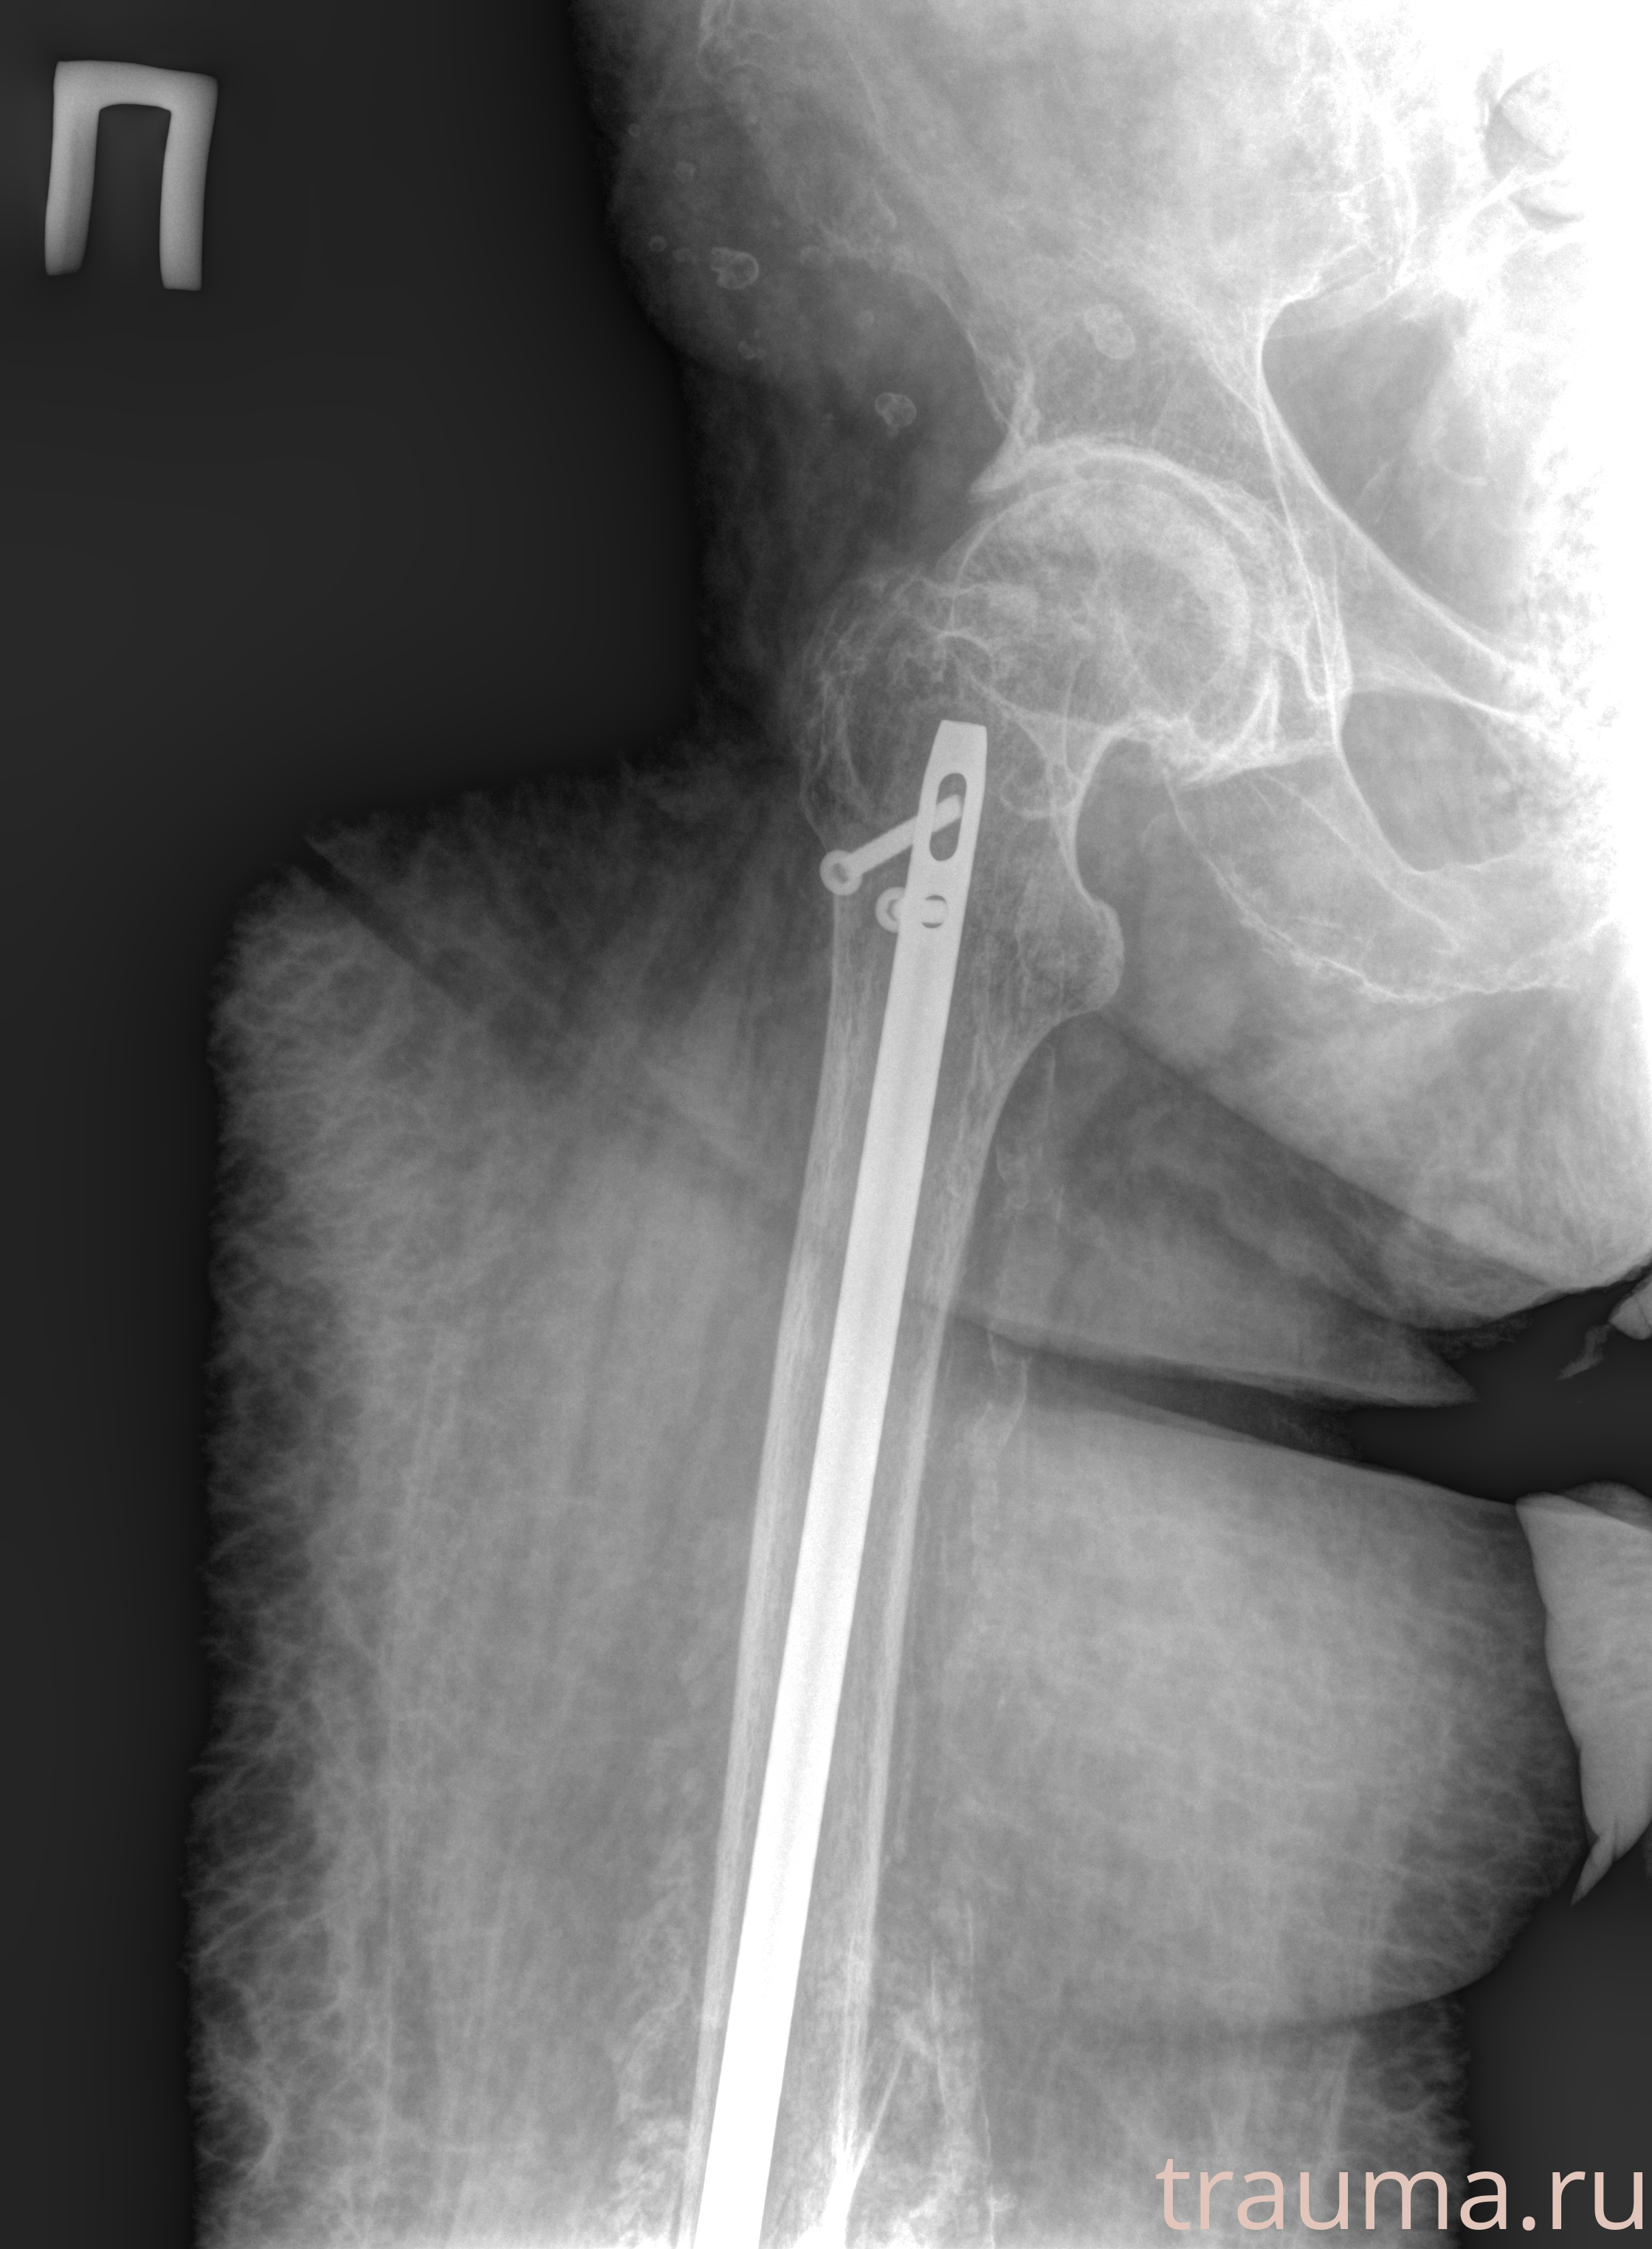

Рентгенограммы

Рентген на дому: по вашему адресу приезжает врач-рентгенолог, травматолог-ортопед с мобильным рентгеновским аппаратом, проводит диагностику травмы или заболевания, делает необходимые рентгенограммы, дает рекомендации по дальнейшему лечению. Получить качественные снимки в домашних условиях возможно благодаря уникальной методике, разработанной МосРентген Центром для института  Склифосовского